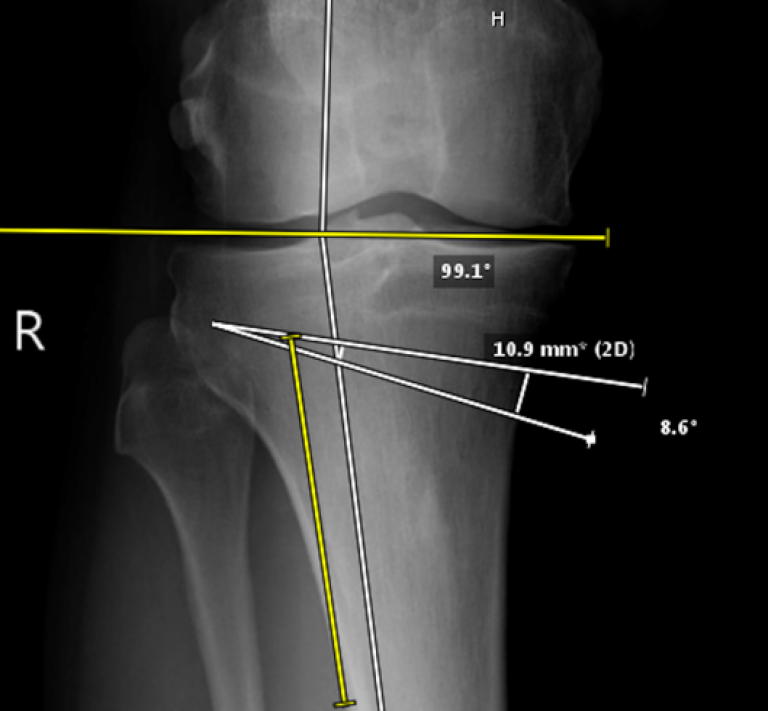

Osteotomy is a crucial operation for early arthritis and pre-arthritic conditions of the knee. For knees with a “bow” deformity – the deformity is usually